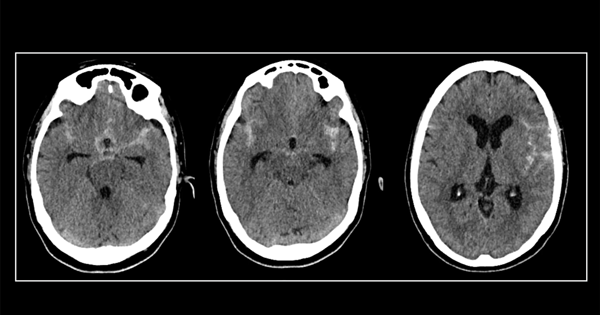

Presentación del caso: paciente masculino de 53 años, con antecedente de accidente cerebrovascular 4 años previo a la consulta en nuestro centro. En contexto de estudio, diagnosticamos un aneurisma grande de bifurcación silviana izquierda, parcialmente trombosado.

Case presentation: a 53-years old male patient presented to our hospital with a history of stroke that occurred 4 years prior to the consultation. A large partially thrombosed sylvian left bifurcation aneurysm was diagnosed.